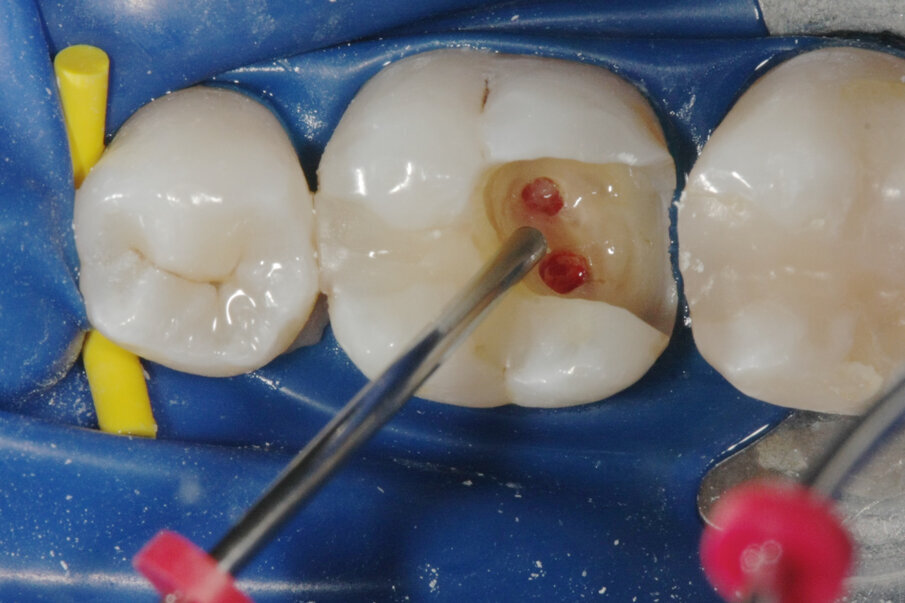

La perforazione accidentale della camera pulpare o del canale radicolare modifica in modo significativo la prognosi del dente. La riparazione della perforazione con un materiale sigillante biocompatibile come MTA può salvare i denti compromessi (Mente et al. 2014) (Figg. 3a-3e).

Riparazione delle perforazioni radicolari